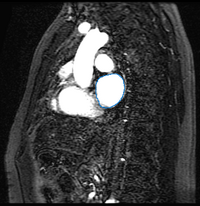

We work with two types of images for each patient: MR angiography (MRA) images where the blood pool has a higher intensity than surrounding tissue and post-procedure delayed enhancement MR images (DE-MRI) where a contrast agent has been injected into the patient to enhance the ablation scar. Our approach is to first segment the left atrium in the MRA images using the label fusion algorithm described in [1]. We then transfer this segmentation to the DE-MRI image of the same patient by registering the two images.

Here we present results we have obtained for one subject using our methods. In the following images, we show the left atrium segmentation in the MRA image as an outline in one slice as well as a 3D model.

Mdepa MRA seg.png Mdepa MRA seg 3D.png